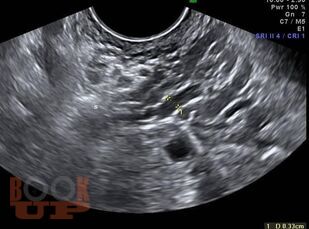

В учебном пособии изложены современные принципы ультразвуковой диагностики вен таза. Представлена анатомия вен малого таза, этиопатогенез, классификация этого заболевания. Приводятся рекомендации о методике ультразвукового исследования вен таза. Учебное пособие предназначено для врачей, обучающихся по программам дополнительного профессионального образования по специальностям «Ультразвуковая диагностика», «Сердечно-сосудистая хирургия».